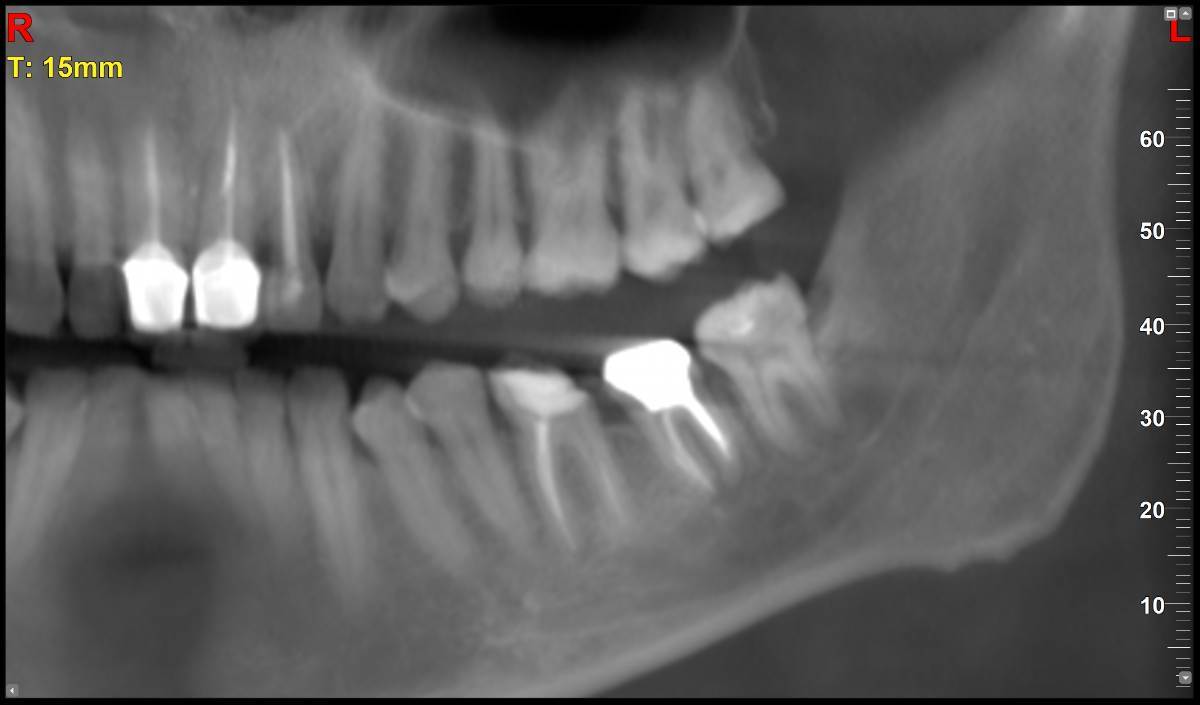

МаксимККК Опубликовано 5 ноября, 2025 Поделиться Опубликовано 5 ноября, 2025 https://disk.yandex.ru/d/6w20ekADUUrt0w Здравствуйте. Установили вкладку на 37 зуб, при снятии слепка под вкладку, ортопед подготовил 2 канала под две ножки вкладки, но с первого раза не получилось снять (ножка сломалась), снял слепок под одну ножку. Вкладку сделали с одной ножкой. Однако, второй канал остался не востребованным и появился вопрос, после сделанного КТ через пару недель после установки вкладки. А запломбировали ли распломбированный канал или он остался просто пустым? И если он остался пустым (ни чем не закрытым), приведет ли это к размножению микроорганизмов в пустоте или другим негативным эффектам? Если оставили пустым, нужно ли снимать вкладку и пломбировать канал? Спасибо. Ссылка на комментарий

МаксимККК Опубликовано 5 ноября, 2025 Автор Поделиться Опубликовано 5 ноября, 2025 1 час назад, Doc сказал: Пустым его оставить не могли, т.к. вкладка сажается на цемент, который закрывает все пустоты. Спасибо за ответ. Сперва подготовили 2 канала, но модель с 2мя ножками под отливку вкладки, не получилась, по этому в этот же прием, во второй раз, сделали на одной. Один канал при установке заполнен ножкой с цементом, а второй уже не понадобился, по этому и спрашиваю, судя по снимкам осталась ли там пустота, после установки (возможно ортопед не отметил в карте, что делал 2 канала и его не запечатал) и если так, чем это чревато. 4 часа назад, red_butler сказал: Здравствуйте, все хорошо, не переживайте. Спасибо за ответ. Ссылка на комментарий

Doc Опубликовано 7 ноября, 2025 Поделиться Опубликовано 7 ноября, 2025 В 05.11.2025 в 23:08, МаксимККК сказал: Спасибо за ответ. Сперва подготовили 2 канала, но модель с 2мя ножками под отливку вкладки, не получилась, по этому в этот же прием, во второй раз, сделали на одной. Один канал при установке заполнен ножкой с цементом, а второй уже не понадобился, по этому и спрашиваю, судя по снимкам осталась ли там пустота, после установки (возможно ортопед не отметил в карте, что делал 2 канала и его не запечатал) и если так, чем это чревато. Спасибо за ответ. Я же написал, не могло там пустоты остаться. Там цемент все заполняет. Ссылка на комментарий